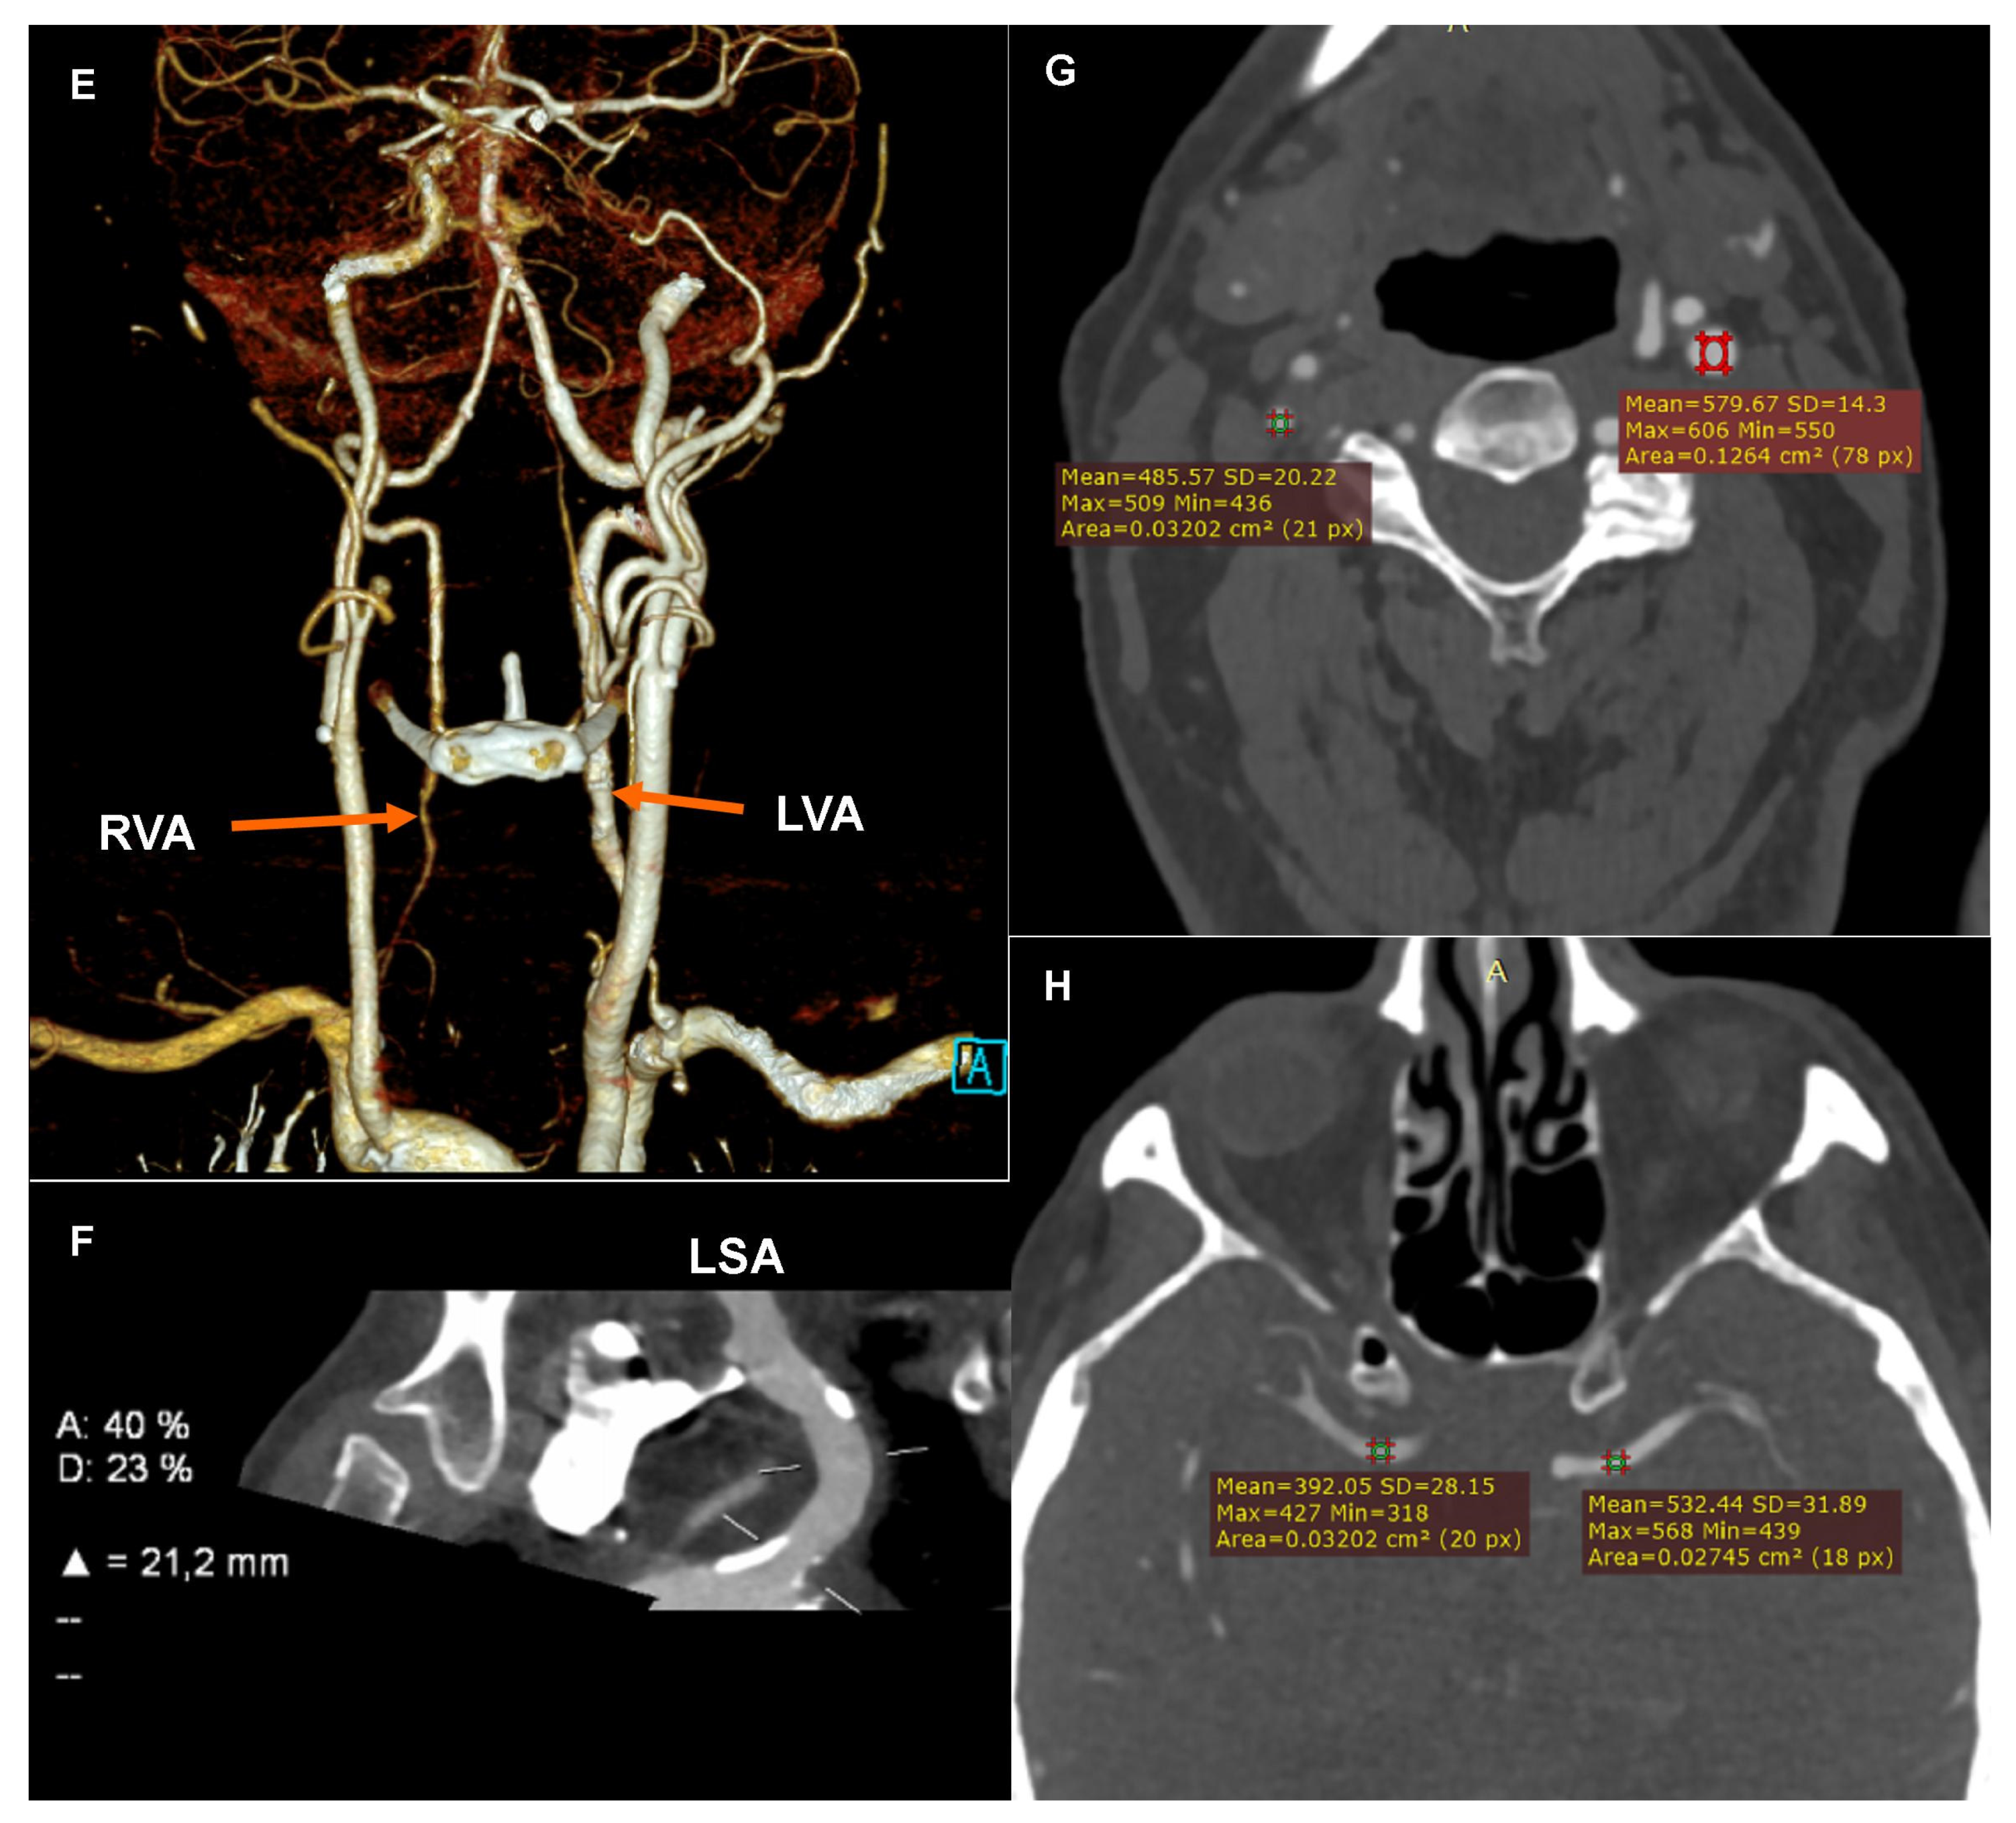

Computed tomography angiography (CTA): (A) Coronary CTA. Native phase. Axial reconstruction. Coronary artery calcium score measurement. The colors indicate the calcifications assigned to specific coronary arteries. (B) Coronary CTA. Angiographic phase. Curved multiplanar reconstruction (cMPR). Left circumflex (LCx). Measurement of the degree of stenosis. (C) Coronary CTA. Angiographic phase. Curved multiplanar reconstruction (cMPR). Left anterior descending (LAD). Measurement of the length of the myocardial muscle bridge. (D) Carotid CTA. Angiographic phase. Curved multiplanar reconstruction (cMPR). Brachiocephalic trunk (BCT). Measurement of the degree of ostial stenosis. The letter A indicates the level of vessel lumen measurement at the reference level, the letter B indicates the level of vessel lumen measurement at the level of maximum stenosis. Computed tomography angiography (CTA): (E) Carotid CTA. Angiographic phase. Volume rendering technique reconstruction (VRT). Arrows mark the recessive right vertebral artery (RVA) and the dominant left vertebral artery (LVA). (F) Carotid CTA. Angiographic phase. Curved multiplanar reconstruction (cMPR). Left subclavian artery (LSA). Measurement of the degree of stenosis. (G) Carotid CTA. Angiographic phase. Axial reconstruction. Measurement of the density of the proximal sections of the internal carotid arteries. Lower density of contrasted blood in the right carotid arteries. (H) Carotid CTA. Angiographic phase. Axial reconstruction. Measurement of the density of the cerebral arteries. Lower density of contrasted blood in the right cerebral arteries.

The CTA of the carotid and vertebral arteries performed using a 384-slice Siemens Force CT revealed a typical origin system of the aortic arch branch, numerous atherosclerotic plaques of various morphotic types in the aortic arch and its branches, significant ostial stenosis of the brachiocephalic trunk by 70–90% of the vessel lumen (Figure 1D), recessive right vertebral artery (Figure 1E), and ostial insignificant stenosis of the left subclavian artery (Figure 1F). In the CTA the right carotid arteries and the right cerebral arteries were characterized by a significantly lower lumen density compared to the contralateral side (Figure 1G,H), which may indicate impaired flow or its direction reversal. The CTA image of the carotid and vertebral arteries corresponded to significant stenosis of the brachiocephalic trunk with symptoms of the steal syndrome.

The complaints reported by the patient could be most likely related to the steal syndrome, which intensified when the patient raised his right arm. Such an explanation of the syncope episode is indicated by the summary of all data from the anamnesis (syncope episode when the patient raised his arms, i.e., when there was a compensatory increase in the reversal of the flow direction in the carotid arteries and subsequent cerebral hypoperfusion), physical examination (lower values of the resting blood pressure measured on the right arm compared to the measurement on the left arm), and imaging examinations (significantly lower flow velocities in the right carotid arteries in the carotid ultrasound and significantly lower lumen density of the right carotid arteries and the right cerebral arteries in the carotid CTA). Blood pressure values were only slightly lower on the right arm than on the left arm. However, it should be remembered that, physiologically, blood pressure values measured on the right arm should be higher; the measurements taken were resting measurements made in the standard position of the upper limbs. Moreover, the patient was treated with antihypertensive drugs due to the diagnosed arterial hypertension.